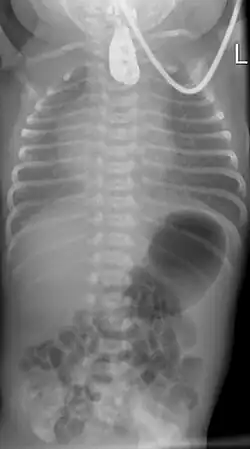

Ösophagusatresie Typ 2 nach Vogt: Kontrastmittel im oberen Blindsack. Keine Luft im Magen-Darm-Trakt.

Zur Diagnosefindung wird die Speiseröhre sondiert. Ein federnder Stopp ist hinweisend. Eine Röntgenaufnahme des Brustkorbes zeigt die Luftfüllung des oberen Blindsackes (sog. Medaillonzeichen), und gegebenenfalls eine Luftfüllung des Darmes als Hinweis auf eine untere Fistel. Nur in Ausnahmefällen wird zusätzlich wasserlösliches Kontrastmittel gegeben.